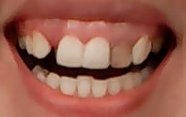

Мне 12 лет. У меня с 6-ти лет возникла такая проблема. Один из 2-х передних зубов стал расти на соседний зуб. Что мне поставят, скобы или брекеты?

• Необходим осмотр и панорамный рентгеновский снимок зубов, оценка прикуса и соотношения зубов. В первую очередь следует лечить центральные резцы так как, по фото, они поражены кариесом. После проконсультируйтесь очно со стоматологом-ортодонтом для составления плана лечения. Скорее всего, в вашем возрасте чаще всего ставят пластины, а брекеты после 14 лет, когда полностью сфор читать далее